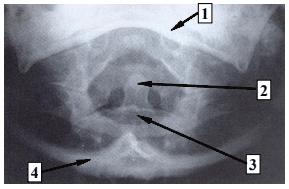

A imagem acima corresponde à incidência do Método de

A

Fuchs.

B

Waters.

C

Twining.

D

Caldwell.